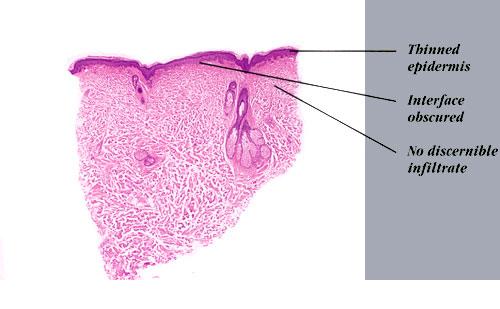

Histopathology. The erythematous-edematous lesions of the skin in dermatomyositis may show only nonspecific inflammation. However, quite frequently the histologic changes are indistinguishable from those seen in SLE. There is epidermal atrophy, basement membrane degeneration, vacuolar alteration of basilar keratinocytes, a sparse lymphocytic inflammatory infiltrate around blood vessels, and interstitial mucin deposition . With severe inflammatory changes, there may be associated subepidermal fibrin deposition. Although immune complexes are not detected at the dermal-epidermal junction as in lupus erythematosus, it should be

remembered that up to 50% of subacute cutaneous lupus biopsies can also have a negative direct immunofluorescence.

Old cutaneous lesions with the clinical appearance of poikiloderma atrophicans vasculare usually show a bandlike infiltrate under an atrophic epidermis with hydropic degeneration of the basal cell layer (see also the section on poikiloderma atrophicans vasculare). The Gottron’s papules overlying the knuckles also show vacuolization of the basal cell layer but acanthosis rather than epidermal atrophy . Subcutaneous tissue may show focal areas of panniculitis associated with mucoid degeneration of fat cells in early lesions. Extensive areas of calcification may be present in the subcutis at a later stage .